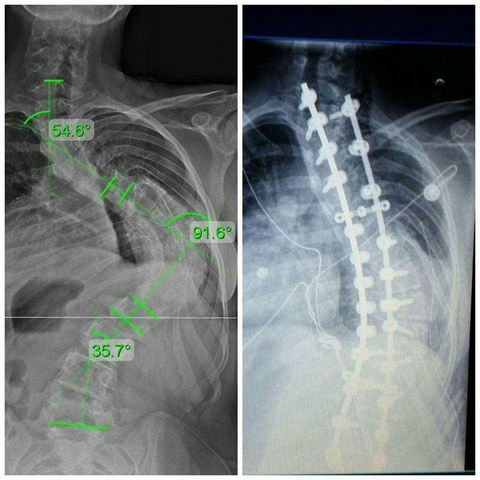

• Diagnosed with Scoliosis

Diagnosed with Scoliosis

At dance class one night in Charlotte, I was stretching when my dance instructor noticed a small hump developing on the right side of my back. She told my mother and I that it was probably scoliosis. Sure enough, when my mother took me to the doctor for an x-ray, we noticed that I had a minor curve in my spine. At this point, I could have had surgery, but I would have multiple surgeries because I was so young. So, I decided to not have the surgery until later and start chiropractic treatment

• First Day of Intensive Therapy

After being diagnosed with scoliosis, I tried bracing. I had to wear a back brace for many hours a day until I got to a point where I would have had to wear it for 23 hours a day. This was too much. That was when I found Maximized Living and their intensive scoliosis therapy. I went down to sunny Orlando, FL for a week on hard and painful stretching and pulling. However, the treatment was able to reduce the curvature of my spine anywhere from 8-12 degrees. I continued this treatment for 5 years.

This was one of the hardest decisions I have ever needed to make in my life. My scoliosis had gotten to a point that at one of my dance competitions, I overheard a judge telling my dance instructor, "Sorry to see the girl with the broken arm." This was because the the giant hump on my back. This caused my arm to bend in a weird shape. At this point, I knew it was time to quit and move on to another chapter in my life.

• Back Surgery

Back Surgery

My back got to a point that my spine started to impact my lung capacity, therefore effecting the way I breathe. This is when I was told that I would need the surgery. Thankfully I only needed one. However, this was a very traumatizing experience. I came out stronger on the other side. I am a lot better physically and mentally now than I was before.